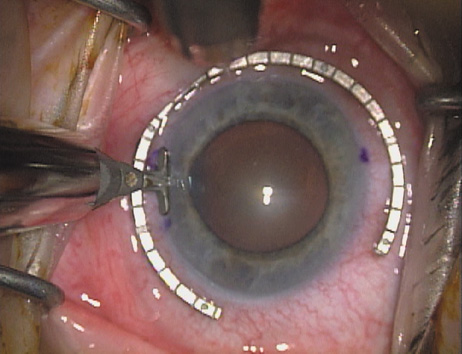

Case 2 is a 79-year-old woman who presented with a very dense left cataract. Her refraction was recorded at −2.25 +2.75 × 125 with a difficult end point. Her manual keratometry and topography measurements were consistent and revealed slightly less than 1.75 D at 120 degrees. Because of the questionable refraction, greater value was placed on the corneal measurements. Based upon the cataract nomogram, the plan was for paired LRIs of 40 degrees to be placed over the steep 120-degree axis (Figs. 1219).

Fig. 14. The incision is completed. (Reprinted from Hardten DR, Lindstrom RL, Davis EA. Phakic Intraocular Lenses: Principles and Practice. Thorofare, NJ: SLACK Incorporated, 2004, with permission.)

Fig. 15. Total arc length equals 40 degrees. (Reprinted from Hardten DR, Lindstrom RL, Davis EA. Phakic Intraocular Lenses: Principles and Practice. Thorofare, NJ: SLACK Incorporated, 2004, with permission.)